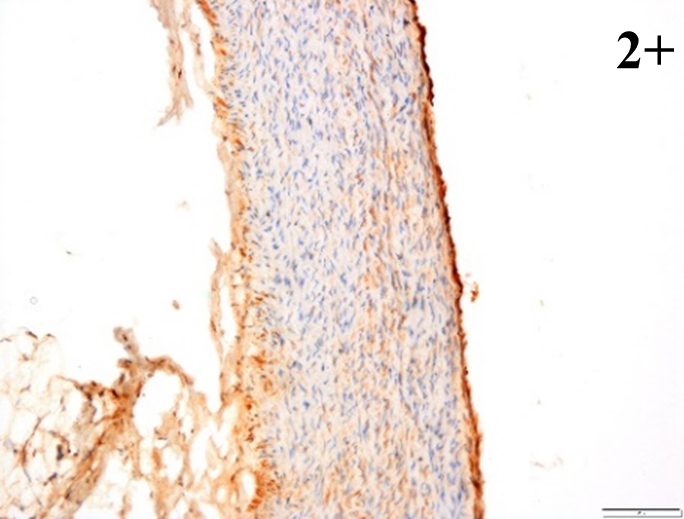

Immunoreactions of ICAM-1, VCAM-1, e-selectin, IL-6, IL-8, NF-

According to the percentage endothelial staining of cells, semi-quantitative

scores were applied. Score: 0 (negative); 1+ (1–10% positive cells); 2+

(11–25% positive cells) and 3+ (

Medium to high expressions of adhesion molecules, such as ICAM-1, VCAM-1 and

e-selectin were observed in the aortas of rabbits fed with HCD. This represents

the initiation of the lesion stage, where the endothelial cells have been

stimulated by the ox-LDL to express the adhesion molecules, which could lead to

the recruitment of monocytes and transmigrate into the intima by diapedesis as

well as differentiate into pro-atherogenic macrophages [47]. An increased

expression of pro-inflammatory biomarkers, such as IL-6, IL-8 and NF-